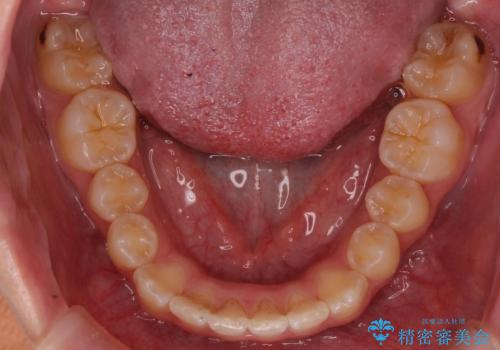

前歯の並び インビザライン 非抜歯で 深いかみ合わせの治療

- 前歯の並びを気にして来院。

上の前歯が内側に倒れこんでいました。

インビザラインで前歯の並びを整えています。

前歯の重なりが大きいいわゆる過蓋咬合を呈していましたが、ある程度適正な重なりにすることができました。